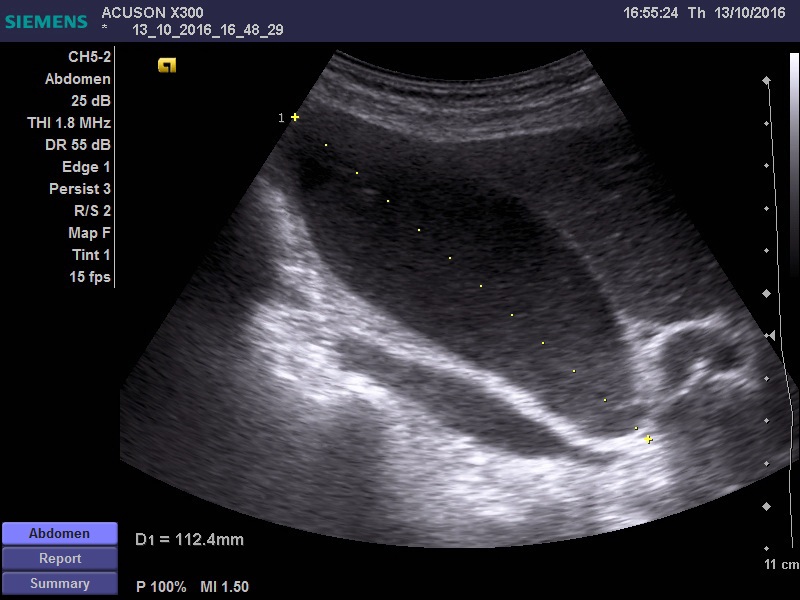

желчный пузырь увеличен 11*5 см, заполнен крупнодисперсной взвесью, в области шейки свободная жидкость. Дискинезия ЖВП?

Не видно причины гипертензии за уровне шейки ЖП -- холедоха, но признаки гипертензии есть.

есть признаки да. учитывая гемодинамически значимый стеноз ВБА, я бы склонился к эмпиеме пузыря, на фоне атеросклеротических изменений пузырной артерии. Учитывая возраст, клиника может быть стёрта, а учитывая наличие свободной жидкости, можно подумать о вялотекущей ишемии стенки и нарастающей деструкции. Я так бы рассудил.

Ишемический некроз стенки желчного пузыря теоретически может быть и он очень плохо диагностируется при УЗИ.

Но должны быть другие признаки воспаления, например, околопузырный инфильтрат и хоть какое-нибудь изменение стенок.